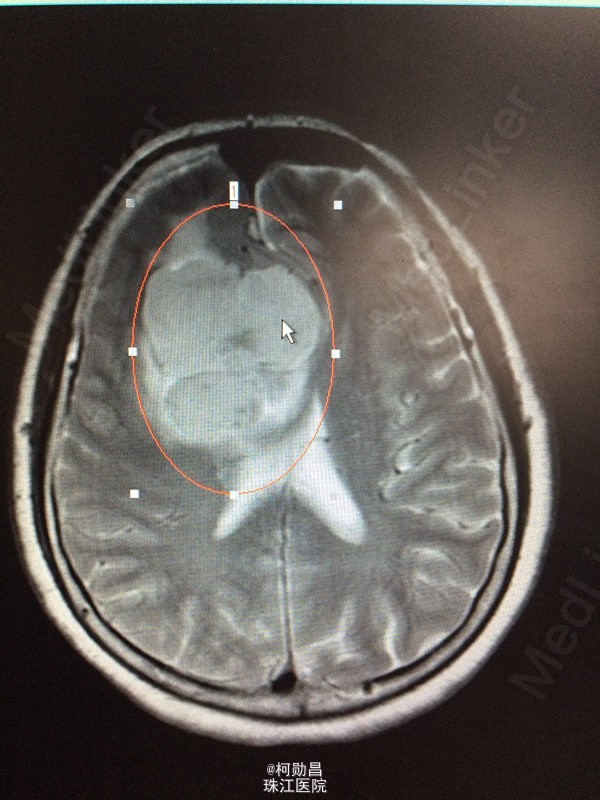

患者 62岁女性,因“发现右侧大脑镰旁肿物2天”入院,症状表现为:反应迟钝,懒言,无其他症状。MR提示“右侧大脑镰旁肿瘤,考虑脑膜瘤”